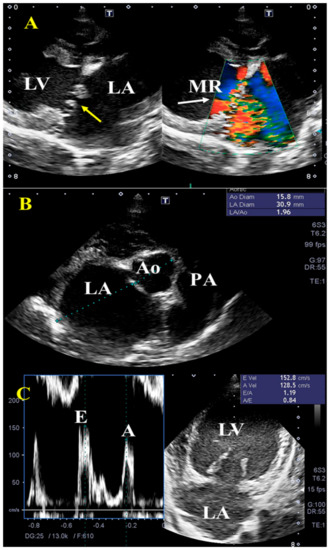

2.2. Echocardiography